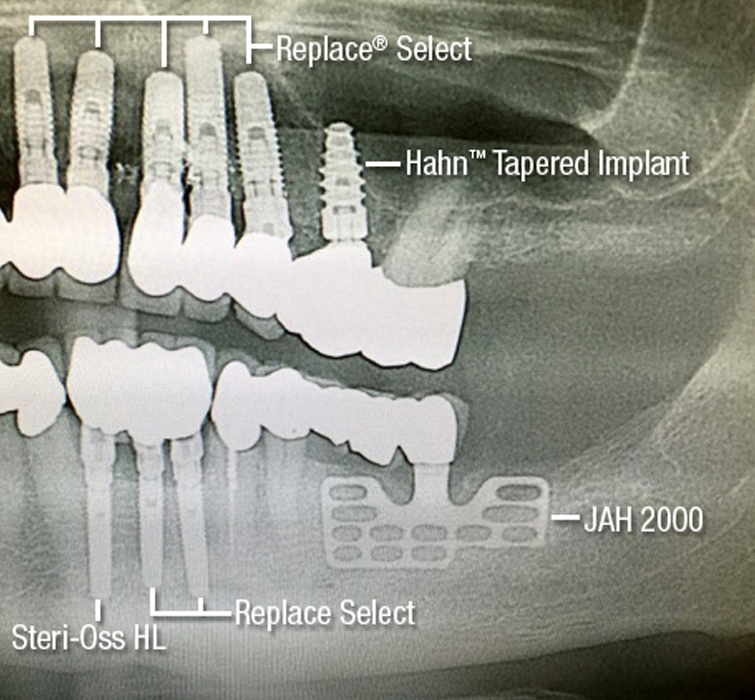

Steri-Oss Implant CSM Image 1 V15I2

This longstanding patient (left) of more than three decades has had various implants placed over the years, including a Steri-Oss implant Dr. Hahn designed with a machined collar. Follow-up radiographs have consistently shown excellent crestal bone preservation around the machined collar of the implants placed in the maxilla, and the Steri-Oss implants have been functioning for nearly 35 years. Note the ample volume of bone above the platform of a Hahn Tapered Implant placed in the posterior (right).